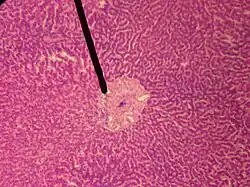

![]() A single lobule of the liver of a pig. X 60. (Central vein not labeled, though region is visible. Central vein would be a single vein at the center of the lobule.) | |

human central vein | |

In microanatomy, the central vein of liver (or central venule)[1] is a vein at the center of each hepatic lobule.[2] It receives the blood mixed in the liver sinusoids to drain it into hepatic veins.[3]